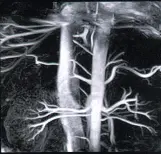

Передовые технологии, доступные в МРТ 1.5 тесла Vantage Elan, позволяют получать достаточные для скрининговой диагностики изображения без внутривенного контрастного усиления, такие как, визуализация сосудов среднего калибра, что существенно улучшает диагностику сосудистой патологии и позволяет заподозрить состояния предпатологии (предрасположенности к возникновению патологии, например – к инсульту, прогрессированию энцефалопатии, деменции и многое другое).

- исследование артерий головного мозга, в том числе артерий 3-4 порядка, без введения контраста

- качественная визуализация сосудов без контраста реализованная благодаря инновационной технологии Advanced Non-Contrast MRI

Исследование головного, спинного мозга и сосудов. Уникальные возможности оборудования позволяют визуализировать сосуды головного мозга и с высочайшей степенью достоверности, диагностировать сосудистую патологию головного мозга, включая сосудистые программы для оценки состояния мелких сосудов.